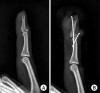

X-ray : 골성 추지(bony mallet)

골성 추지(bony mallet finger) : 뼈조각의 크기가 관절면의 1/3 이상이거나 탈구가 있으면 수술적 치료가 필요합니다,